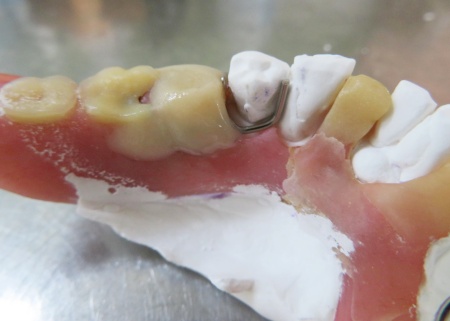

内側のクラスプの位置を確認しました